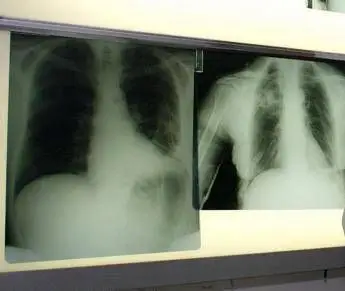

Bpco, ok dell'Ema alla prima terapia con propellente green

(Adnkronos) - L'esperto: "Passo importante per combinazione fissa budesonide/glicopirronio/formoterolo fumarato e per prodotti respiratori inalatori"